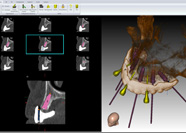

Il nostro laboratorio odontotecnico, utilizza quotidianamente tecnologie e materiali all'avanguardia, per soddisfare un mercato sempre più esigente e in costante evoluzione. Cerchiamo costantemente di mettere la nostra passione ed esperienza a disposizione di un clinico sempre più aggiornato, informato e desideroso di ricevere un dispositivo di qualità, che rispecchi il prestigio del proprio studio. CAD-CAM, consente di realizzare lavori di estrema precisione, estetici e di ottima qualità, senza dimenticare le tradizionali lavorazioni che ci accompagnano nella quotidianità.